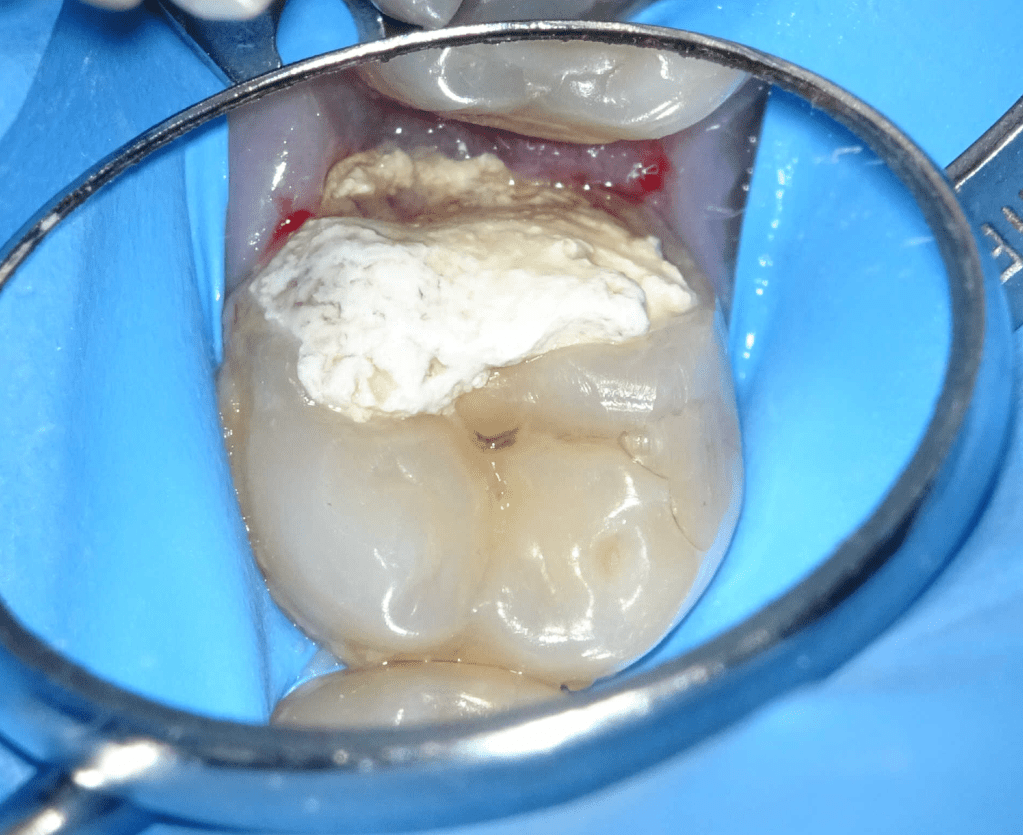

Pulpotomía biodentine + reco preendio